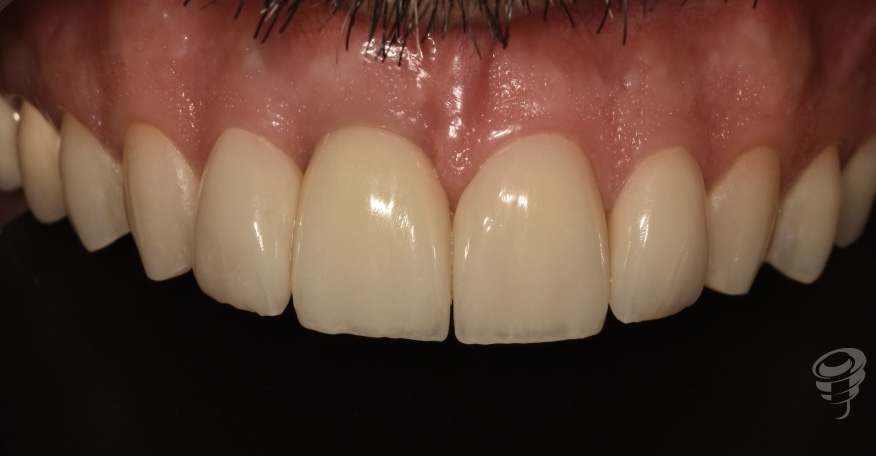

Revisión a los 24 meses

Figura 50

Figura 51

Figura 52

Figura 53